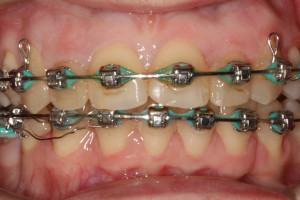

Młoda pacjentka zgłosiła się do naszego gabinetu celem wykonania kompleksowego leczenia zachowawczo-ortodontycznego. Oprócz problemów natury ortodontycznej stwierdzono złą higienę jamy ustnej oraz liczne potrzeby leczenia zachowawczo-endodontycznego. Po wnikliwej analizie telerentgenowskiej oraz analizie modeli zadecydowano o ekstrakcji 2 zębów w łuku dolnym (kła po stronie lewej oraz pierwszego przedtrzonowca po stronie prawej). Plan leczenia obejmował ponadto zamknięcie łuku po brakujących zębach w łuku górnym. Leczenie aktywne trwało 2 lata i 8 miesięcy. W czasie jego trwania pacjentka była regularnie poddawana zabiegom higieny profesjonalnej celem eliminacji zapaleń przyzębia brzeżnego. Po leczeniu aktywnym zastosowano leczenie retencyjne w postaci retainera stałego w żuchwie oraz szyny retencyjnej w łuku górnym.